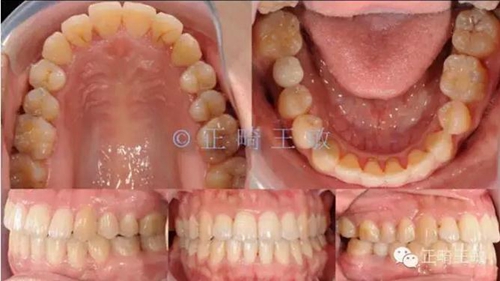

有了一個(gè)目標(biāo)后,矯正就很簡(jiǎn)單了,拔掉一顆牙,7個(gè)月順利讓牙齒移動(dòng)到我們想要的位置:

9.jpg

雖然這個(gè)時(shí)候正畸并沒有結(jié)束,但對(duì)于種植來(lái)說(shuō),間隙和排列,已經(jīng)足夠了,畢竟種植周期也要4個(gè)月,后面的治療就是繼續(xù)關(guān)閉間隙,調(diào)整咬合,同時(shí)等著那顆種植牙生根發(fā)芽。來(lái)看看最終的樣子: